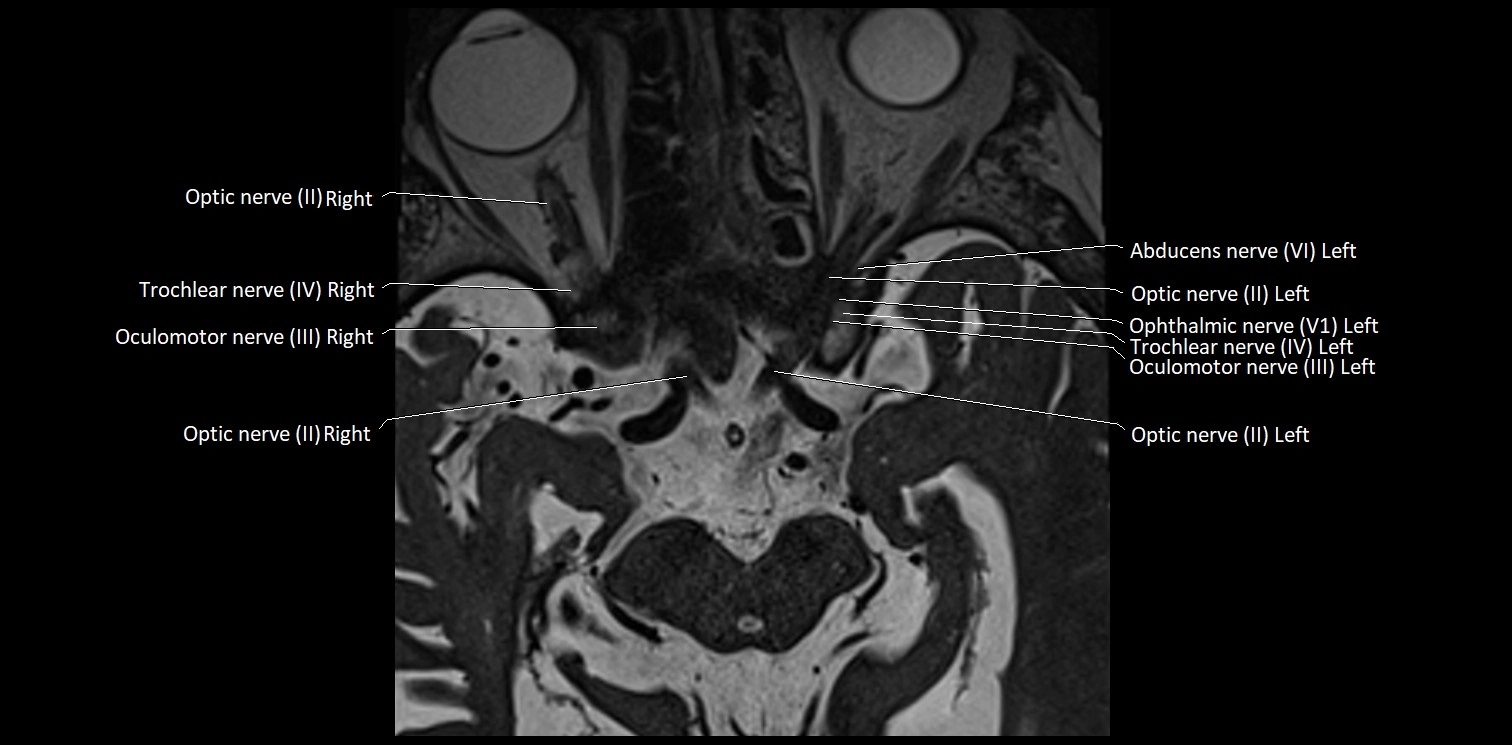

MRI Appearance

• The abducens nerve is a small, thin, linear structure

• Best visualized on high-resolution T2-weighted 3D MRI sequences (e.g., FIESTA or CISS)

• Seen as a hypointense (dark) line running from the brainstem at the pontomedullary junction, traversing the prepontine cistern, and entering Dorello’s canal under the petrosphenoidal ligament, then into the cavernous sinus, and finally the orbit

• May be challenging to visualize in standard MRI due to its small size

• Pathology may be inferred by absence, displacement, or enhancement of the nerve

MRI images

image